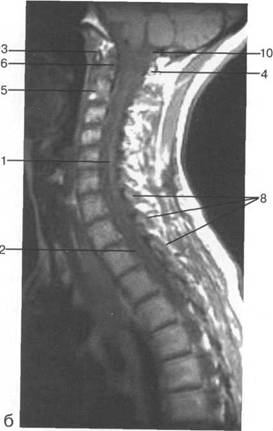

MPT.

ThXI1;

ThK-Thx.

Thlx; Thlx;